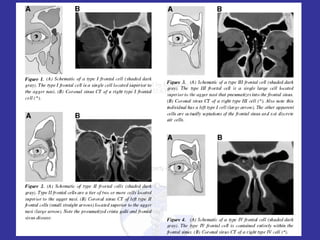

Frontal Cells Anatomy May contribute to mechanical obstruction of the frontal recess Classification (Bent and Kuhn) Type I:  single cell superior to agger nasi Type II:  2 or more cells Type III:  single large that pneumatizes into the frontal sinus Type IV:  cell contained completely within the frontal sinus

Frontal Cells AnatomyMay contribute to mechanical obstruction of the frontal recess Classification (Bent and Kuhn) Type I: single cell superior to agger nasi Type II: 2 or more cells Type III: single large that pneumatizes into the frontal sinus Type IV: cell contained completely within the frontal sinus

Frontal Cells Meyer (Am J Rhino 2003) 768 CT scans met study criteria Objective:  are frontal cells associated with variants of pneumatization? Frontal cells present in 20.4% of study population Positively associated with hyperpneumatization of the frontal sinus and negatively with hypopneumatization Increased prevalence of concha bullosa In general, type III and IV individuals had increased prevalence of frontal mucosal thickening but not maxillary or ethmoid thickening

Frontal Cells Meyer(Am J Rhino 2003) 768 CT scans met study criteria Objective: are frontal cells associated with variants of pneumatization? Frontal cells present in 20.4% of study population Positively associated with hyperpneumatization of the frontal sinus and negatively with hypopneumatization Increased prevalence of concha bullosa In general, type III and IV individuals had increased prevalence of frontal mucosal thickening but not maxillary or ethmoid thickening